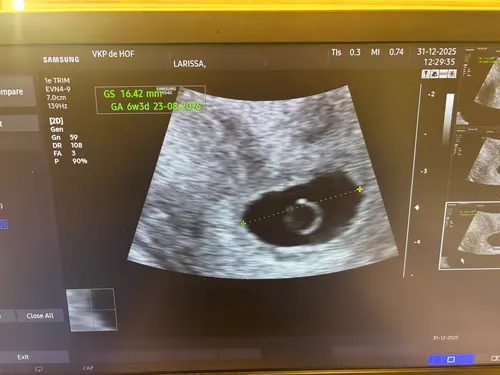

maar tijdens de echo van vandaag werd gezegd dat:

• het hartje nog steeds niet klopt

• en dat het embryo niet (of nauwelijks) gegroeid is sinds vorige week

Daarom gaf de verloskundige aan dat de kans ongeveer 99% is dat dit zal uitlopen op een miskraam.

Eerste echo is van 22 december andere echo van 31 december